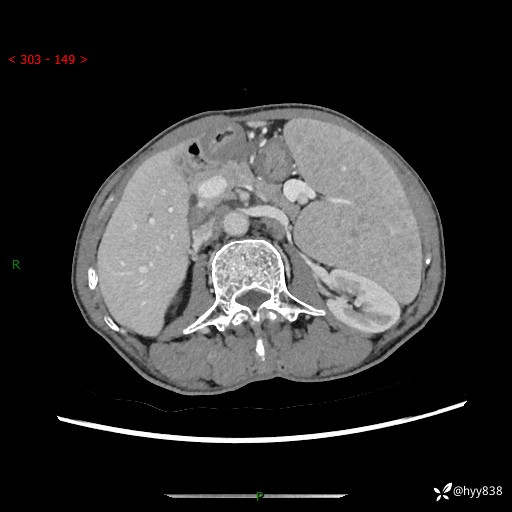

老年男性,脾大并脾脏弥漫粟粒状低密度,淋巴瘤 VS 肉芽肿 VS 血管瘤---结果公布

简要病史: 患者于3月前无明显诱因出现脾大,伴腹部轻微不适,具体不详,无腹痛、腹泻、腹胀,无头晕、头痛、乏力,无恶心、呕吐、呕血,无胸闷、气短、胸痛不适

上腹部CT平扫+增强